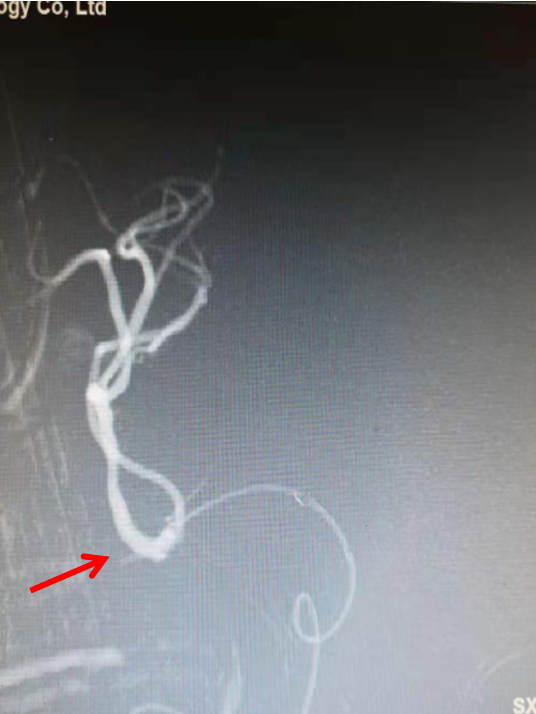

headway17微导管在3m的Synchro-14导丝辅助下,谨慎通过闭塞处,撤出微导丝,微导管造影证实在真腔(左图),而后将微导丝置于闭塞血管远端后撤出微导管(右图)。